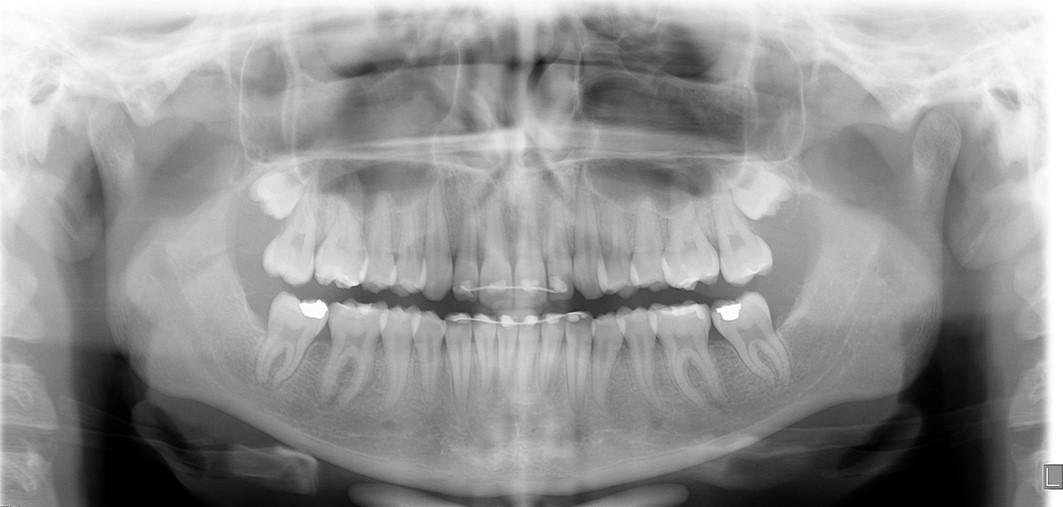

A healthy 12-year-7-month-old female, with an adult dentition, presented with a chief complaint of “teeth not coming in straight,” as was identified to her and her parents by a referring dentist. On clinical examination, the patient had pleasing facial esthetics on an orthognathic skeletal base. Intraorally, the patient had Angle Class I molar relationship bilaterally with well-aligned arches but impacted mandibular second molars with partially visible crowns (Figure 1). The panoramic radiograph confirmed the mesioangular impactions of the mandibular second molars bilaterally along with the third molars at the early crown calcification stage of development (Figure 1). An increase in inclination of second molars can be seen bilaterally, on examination of panoramic radiographs at ages of 10 years and 5 months and 11 years 10 months, which were 17 months apart (Figures 1 and 2).

Given the clinical and radiographic presentations, the treatment plan to surgically extract the developing third molars prior to orthodontic treatment was presented to the patient and parents for their consent. The mandibular third molars were surgically removed by an oral surgeon under deep sedation. A follow-up panoramic radiograph obtained approximately 7 months following the surgery, at 12 years and 7 months of age, revealed completely healed third molar extraction sites, spontaneous improvement in the angulation of the left mandibular second molar but little change in the angulation of the right second molar. Orthodontic records were obtained at this stage and treatment was initiated with complete maxillary and mandibular orthodontic MBT, 0.022’’ slot size brackets. Orthodontic bands were placed on the mandibular first permanent molars that were modified with laboratory soldered Halterman appliances from the lingual surfaces of the bands. Orthodontic buttons were bonded on the occlusal surfaces of the impacted molars. Initial disimpaction of the second molars was achieved by sequential distal traction with the use of chain elastics. When the molars were sufficiently uprighted and the buccal surfaces were visible, orthodontic direct-bond brackets were placed and the Halterman arm and occlusal buttons were removed. All further orthodontic tooth movements including uprighting of the second molars were achieved through 4-6-weekly sequential changes of Nickel-Titanium followed by stainless steel archwires. The sequence of archwires were as follows: Ni-Ti0.012”, 0.014”, 0.016”, 0.018” 0.016x0.022”, 0.017x0.025 and SS- 0.016x0.022”, 0.017x0.025, all wires ligated with elastics. Bonded lingual wire retainers, as well as removable Essix retainers, were delivered to the patient to maintain the results.

The left photo shows the impacted second molars, post third molar extraction surgery but pre-orthodontic treatment. The photograph on the right shows 5-year follow-up post-orthodontic treatment. Note mesio-occlusal caries restored with amalgam restorations during the course of orthodontic treatment.

Fig. 5a: Age: 12 years, 7 months

Fig. 5b: Age: 17 years 7 months